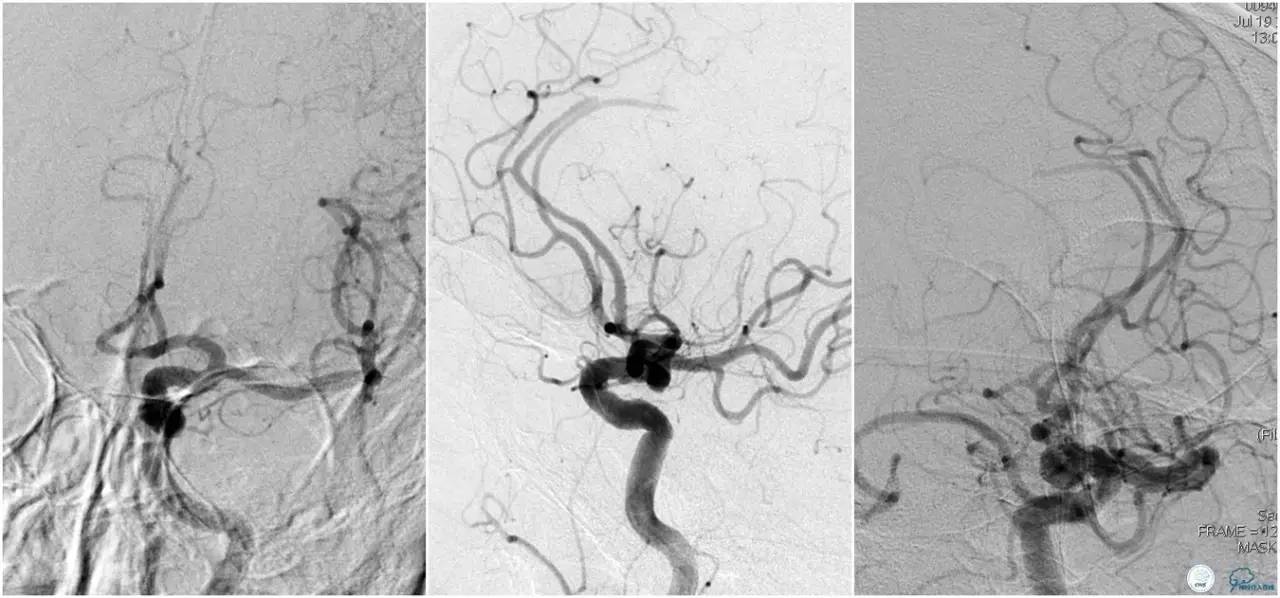

6F Envoy置于颈内动脉C3段,选用Solitaire-FR 4*20mm支架释放于右侧大脑前动脉,完全覆盖血栓。

6F Envoy置于左侧颈内动脉C3段,选用Solitaire-FR 4*20mm支架释放于右侧大脑前动脉取栓1次,血流达TICI 2b。

Solitaire-FR 4*20mm支架释放于左侧大脑前动脉取栓1次,取出少许血栓重复造影左侧大脑前动脉胼周动脉开口后,右侧大脑前动脉A2段以远未显影,考虑栓子逃逸。

选用Solitaire-FR 4*20mm支架分别于右侧大脑前动脉A2-A3段,左侧胼周动脉,右侧胼周动脉取栓3次。

双侧大脑前动脉完全显影,TICI 3级,TOR 261min。